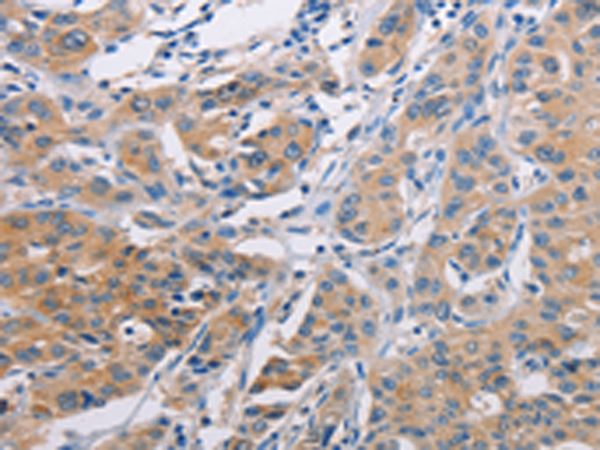

分类: 科研抗体货号: P07782别名:应用: IHC反应种属: Human, Mouse